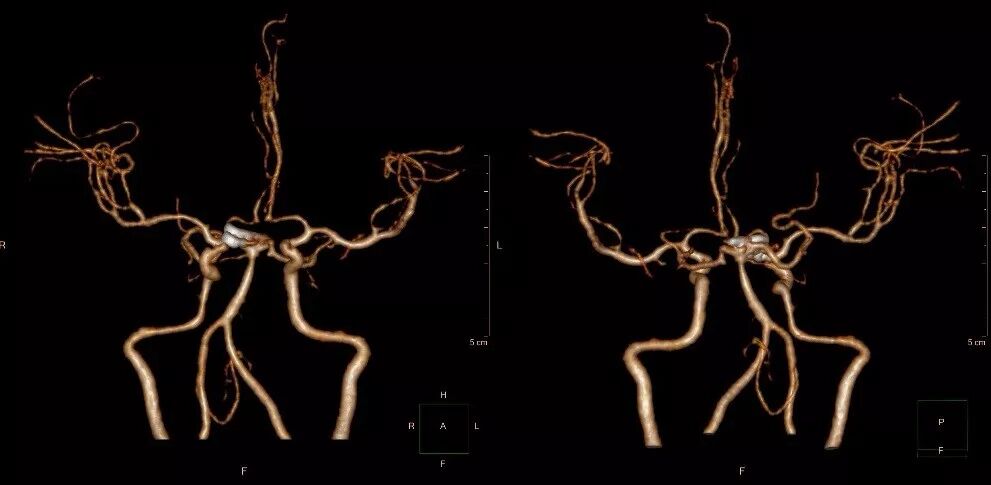

图1-4. 术后头颅CTA可见左侧颈内后交通动脉瘤、右侧小脑上动脉瘤夹闭完全。

图3-8. 术后头颅CTA复查可见动脉瘤夹闭满意

图3-9. 手术骨窗重建